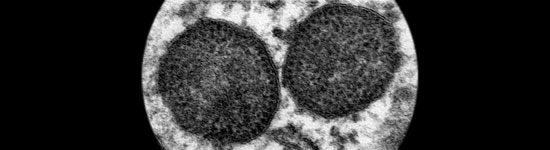

Coinfección y vacunación combinada frente a PCV2 y Mycoplasma hyopneumoniae

La infección experimental por Mhyo y PCV2 ha proporcionado resultados un tanto divergentes.

El PCV2 se ha ido asociando cada vez a más patologías, denominadas colectivamente enfermedades asociadas a PCV2 (PCVDs), como ES-PCV2, EP-PCV2, EE-PCV2, ER-PCV2, IS-PCV2 y SDNP.